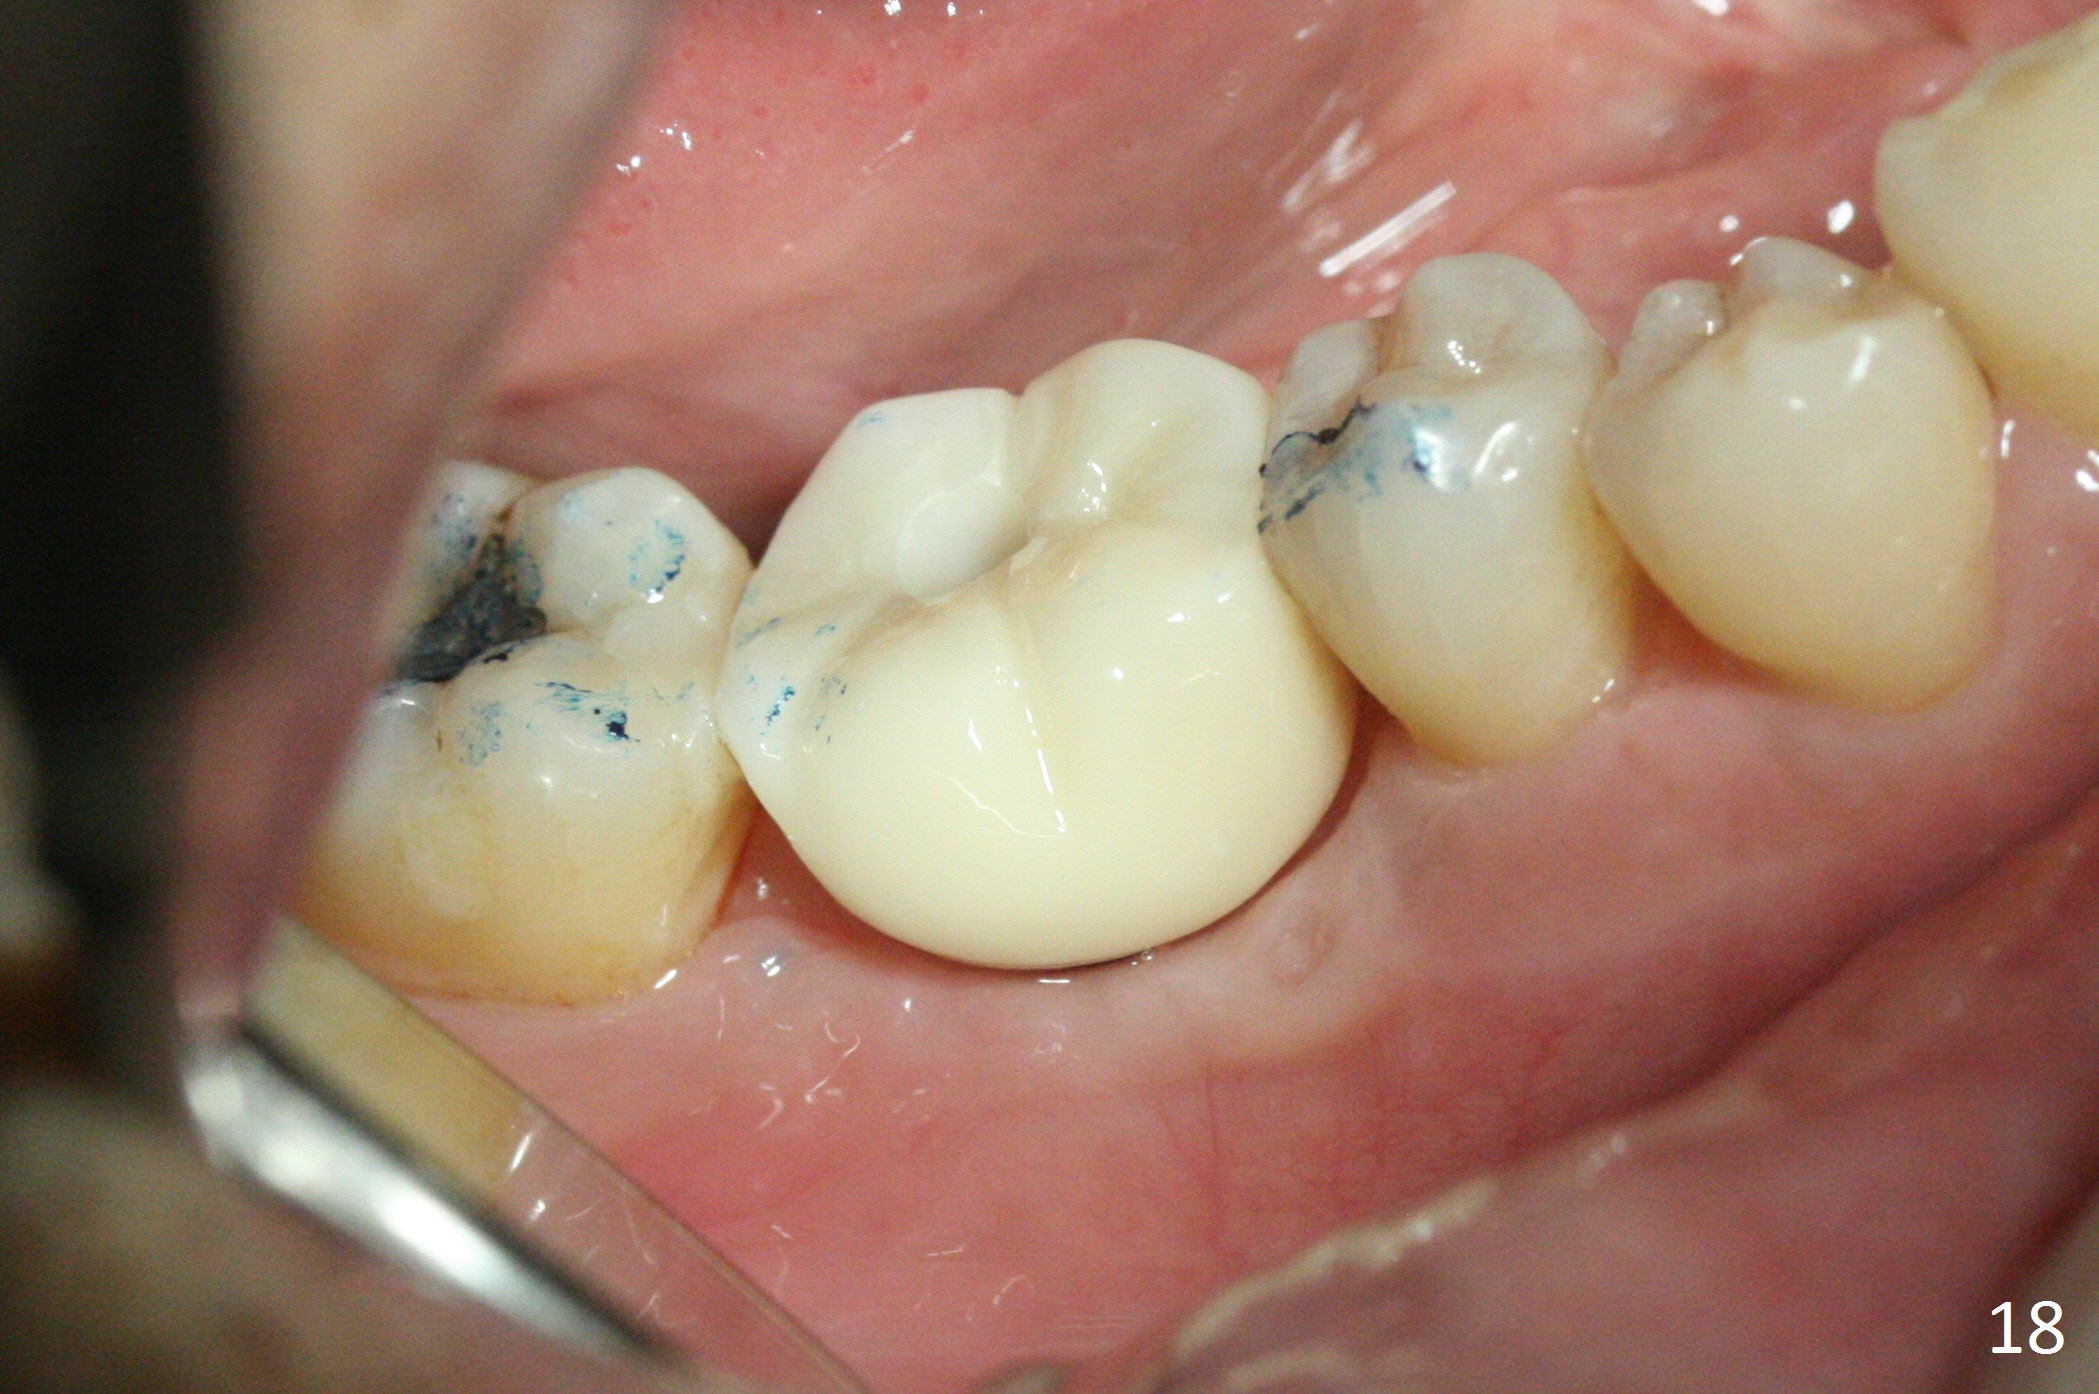

Three weeks later (5.5 months postop), a permanent crown tries in with healthy keratinized gingiva (Fig.18). The provisional keeps normal gingival bed (Fig.19), while the abutment forms tissue cuff (Fig.20). After cementation, PA shows bone regeneration (Fig.21). The gingiva remains healthy 8.5 months post cementation (Fig.22). Bone density around the implant increases 1 year 2 months post cementation (Fig.24). The gingiva remains healthy 2 years 4 months post cementation (Fig.25).